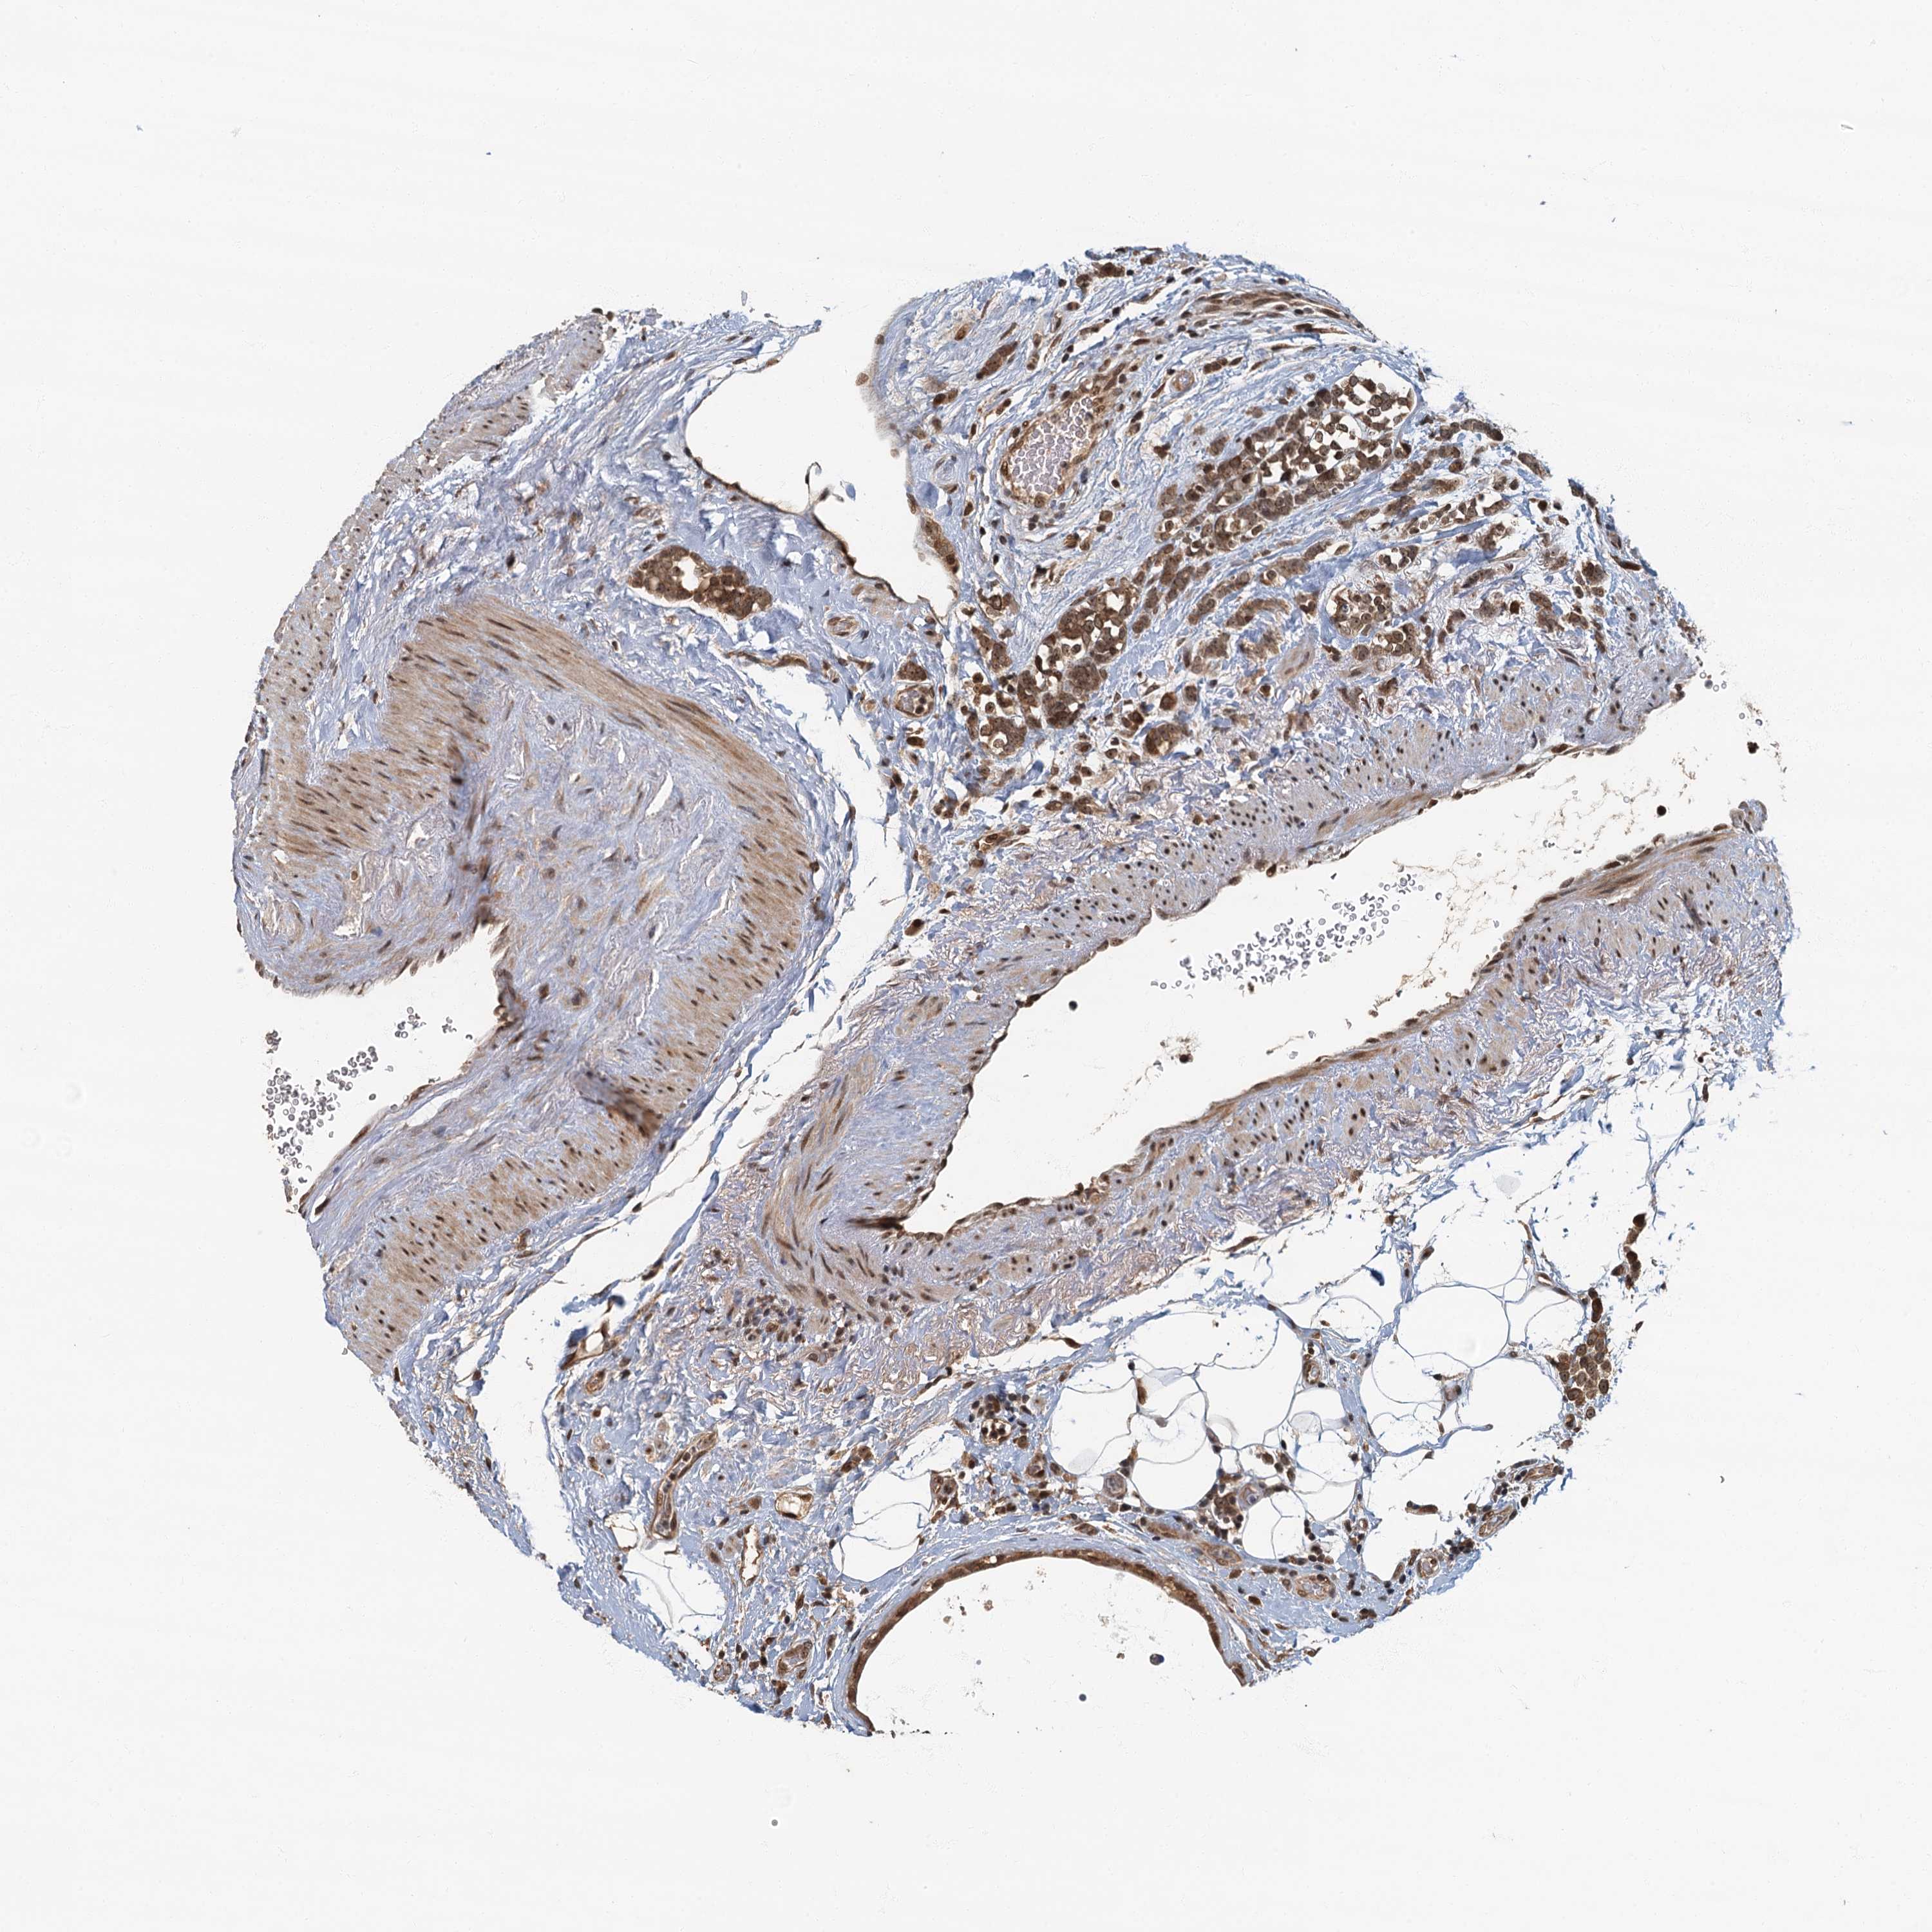

CANCER BREAST CANCER Show tissue menu

BRCA TCGA BRCA VALIDATION PROTEIN EXPRESSION

ANTIBODIES

AND

VALIDATION